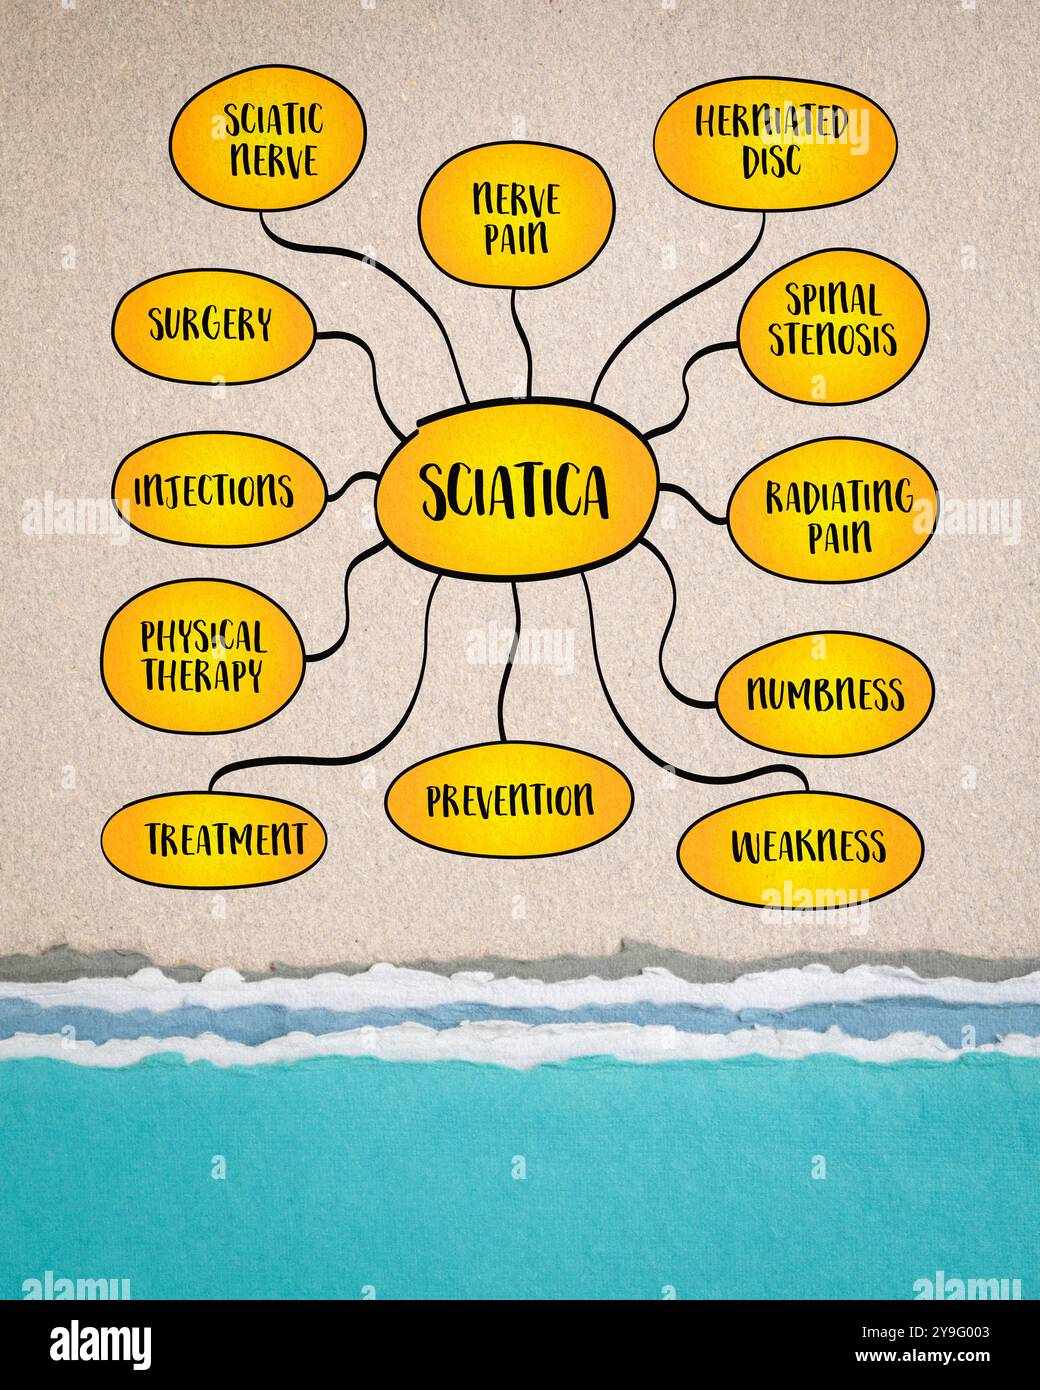

Sciatique se réfère à la douleur qui rayonne le long du chemin du nerf sciatique, le plus grand nerf dans le corps, infographie de carte mentale. Banque D'Imageshttps://www.alamyimages.fr/image-license-details/?v=1https://www.alamyimages.fr/sciatique-se-refere-a-la-douleur-qui-rayonne-le-long-du-chemin-du-nerf-sciatique-le-plus-grand-nerf-dans-le-corps-infographie-de-carte-mentale-image625456387.html

Sciatique se réfère à la douleur qui rayonne le long du chemin du nerf sciatique, le plus grand nerf dans le corps, infographie de carte mentale. Banque D'Imageshttps://www.alamyimages.fr/image-license-details/?v=1https://www.alamyimages.fr/sciatique-se-refere-a-la-douleur-qui-rayonne-le-long-du-chemin-du-nerf-sciatique-le-plus-grand-nerf-dans-le-corps-infographie-de-carte-mentale-image625456387.htmlRF2Y9G003–Sciatique se réfère à la douleur qui rayonne le long du chemin du nerf sciatique, le plus grand nerf dans le corps, infographie de carte mentale.